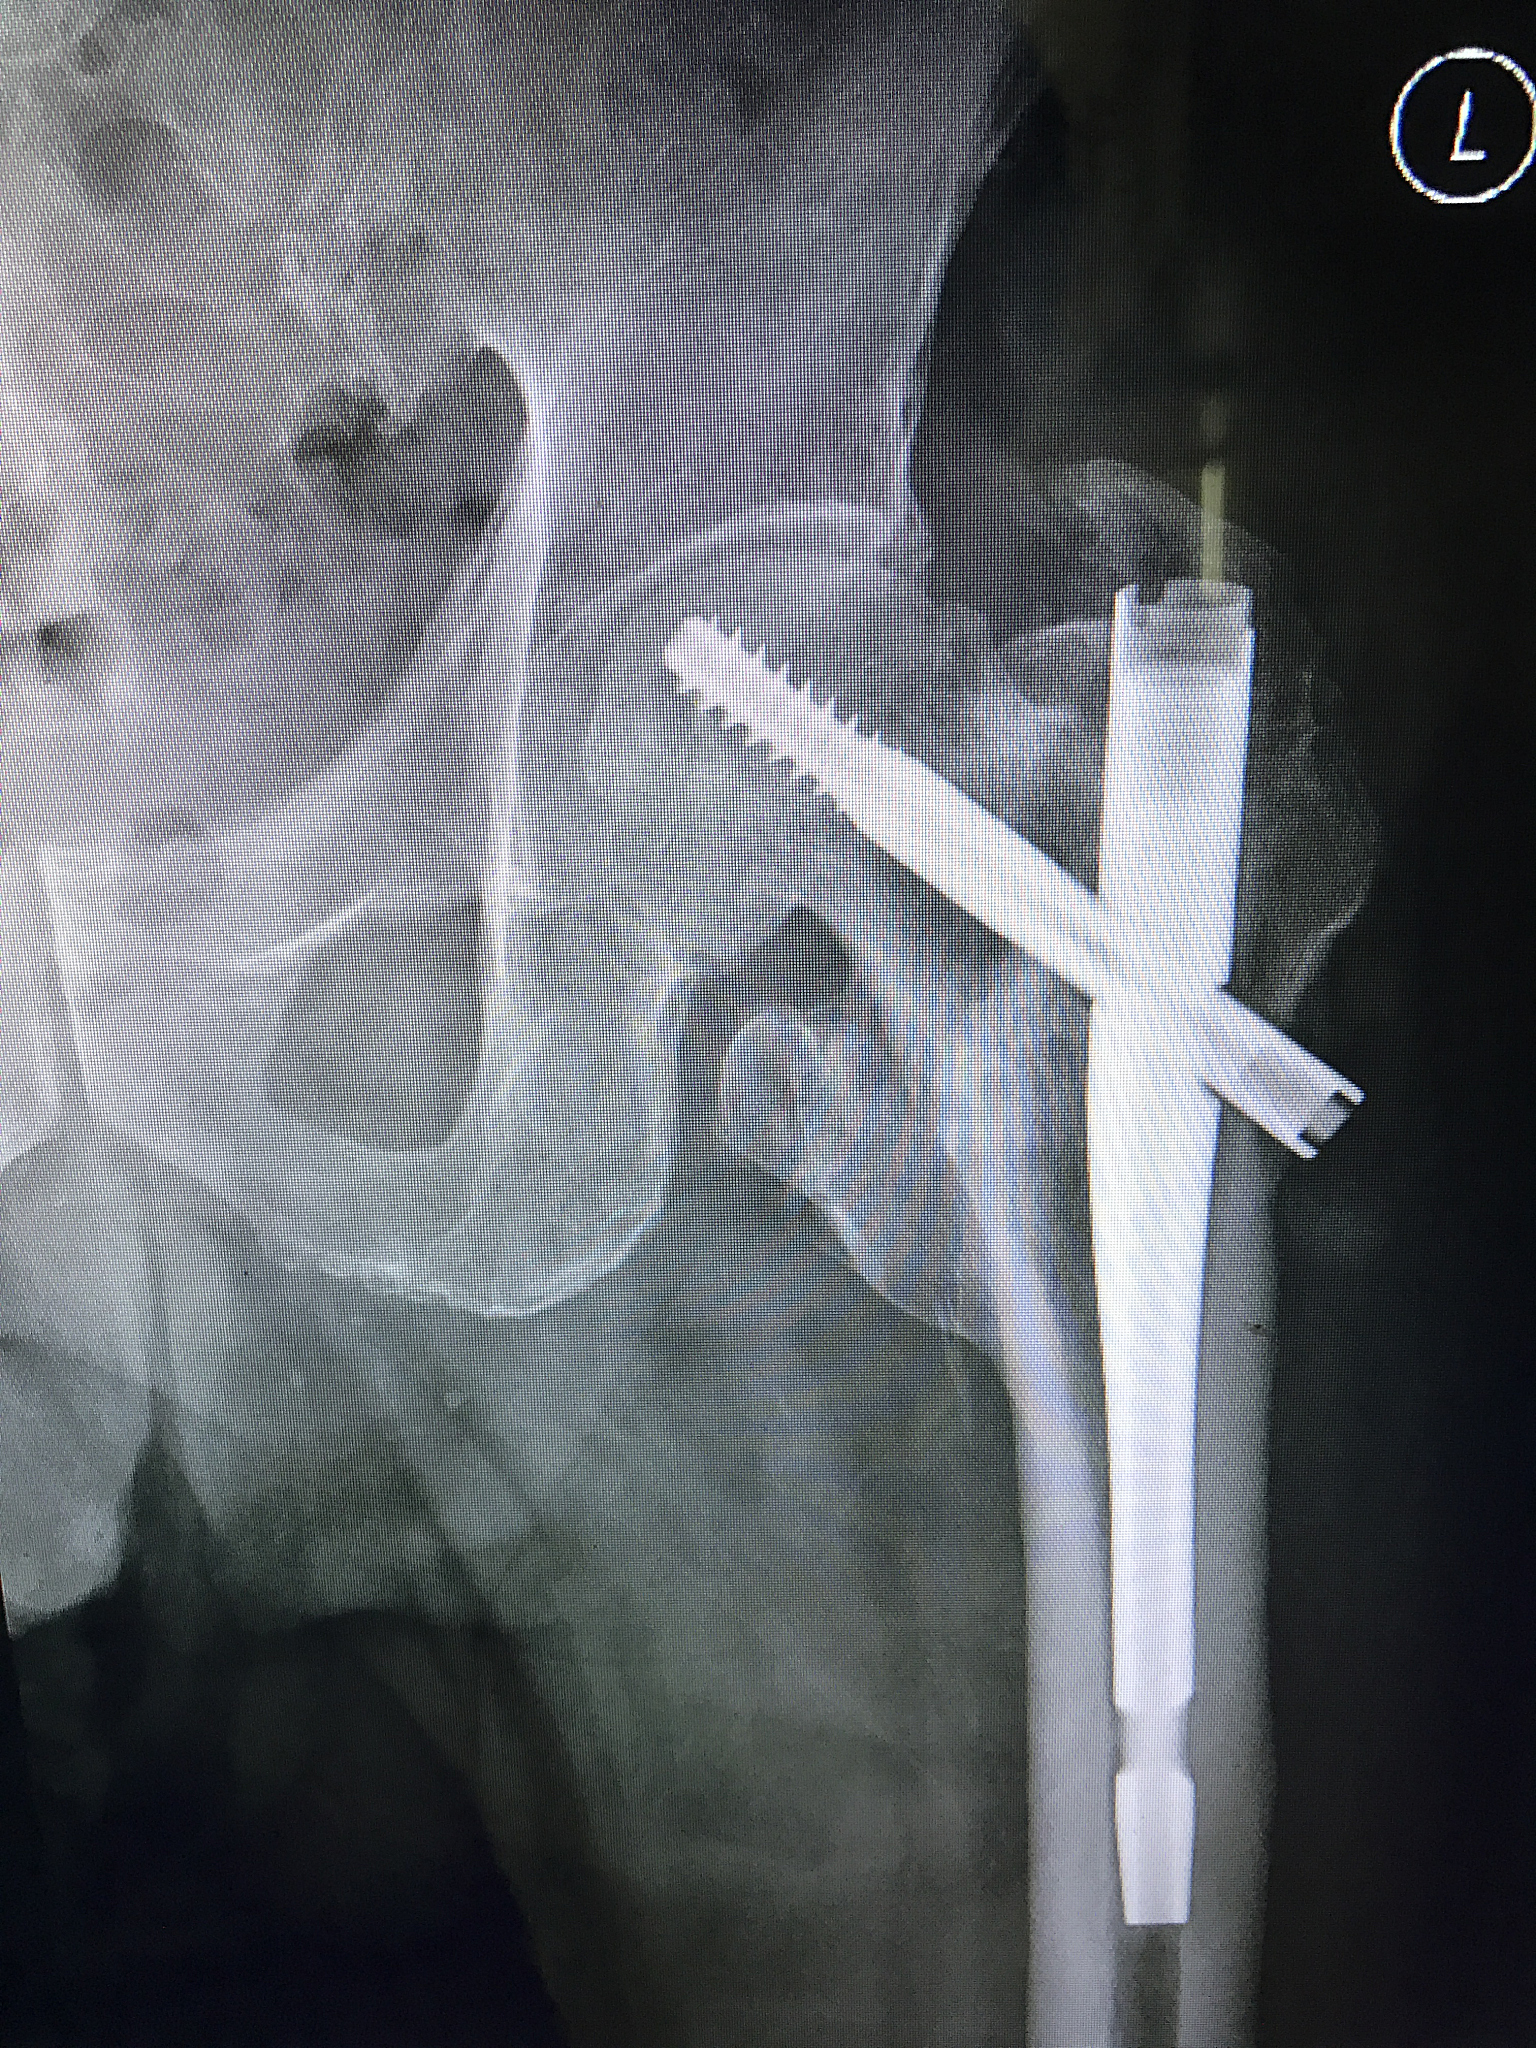

2. 促进骨折愈合: ORIF手术能够将骨折的碎片精确复位并固定,使骨折端的血供得到恢复,从而促进骨折愈合。内固定物 (例如钢板、螺钉) 可以提供稳定的支撑,避免骨折端的移位,为骨痂生长创造良好环境。